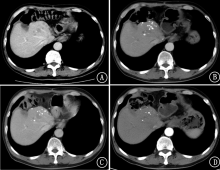

大多数肝癌患者发病时已为中晚期,且缺乏有效治疗手段,预后极差。本研究报道采用甲磺酸阿帕替尼联合卡瑞利珠单抗二线以上治疗1例原发性肝癌伴肺转移病例,取得了显著疗效,为晚期原发性肝癌的治疗提供了新的方法。